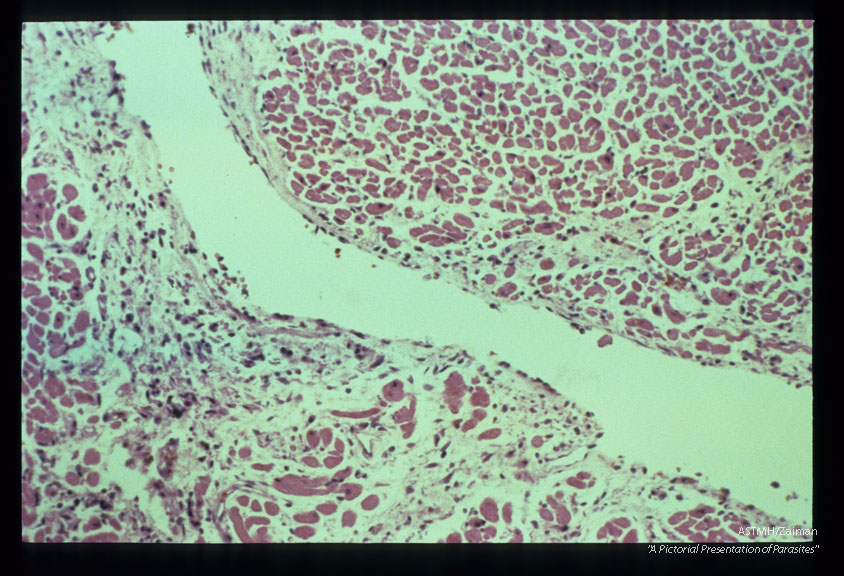

Endomyocarditis. Lymphoplasmocytic infiltrate.

Description: Endomyocarditis. Lymphoplasmocytic infiltrate.